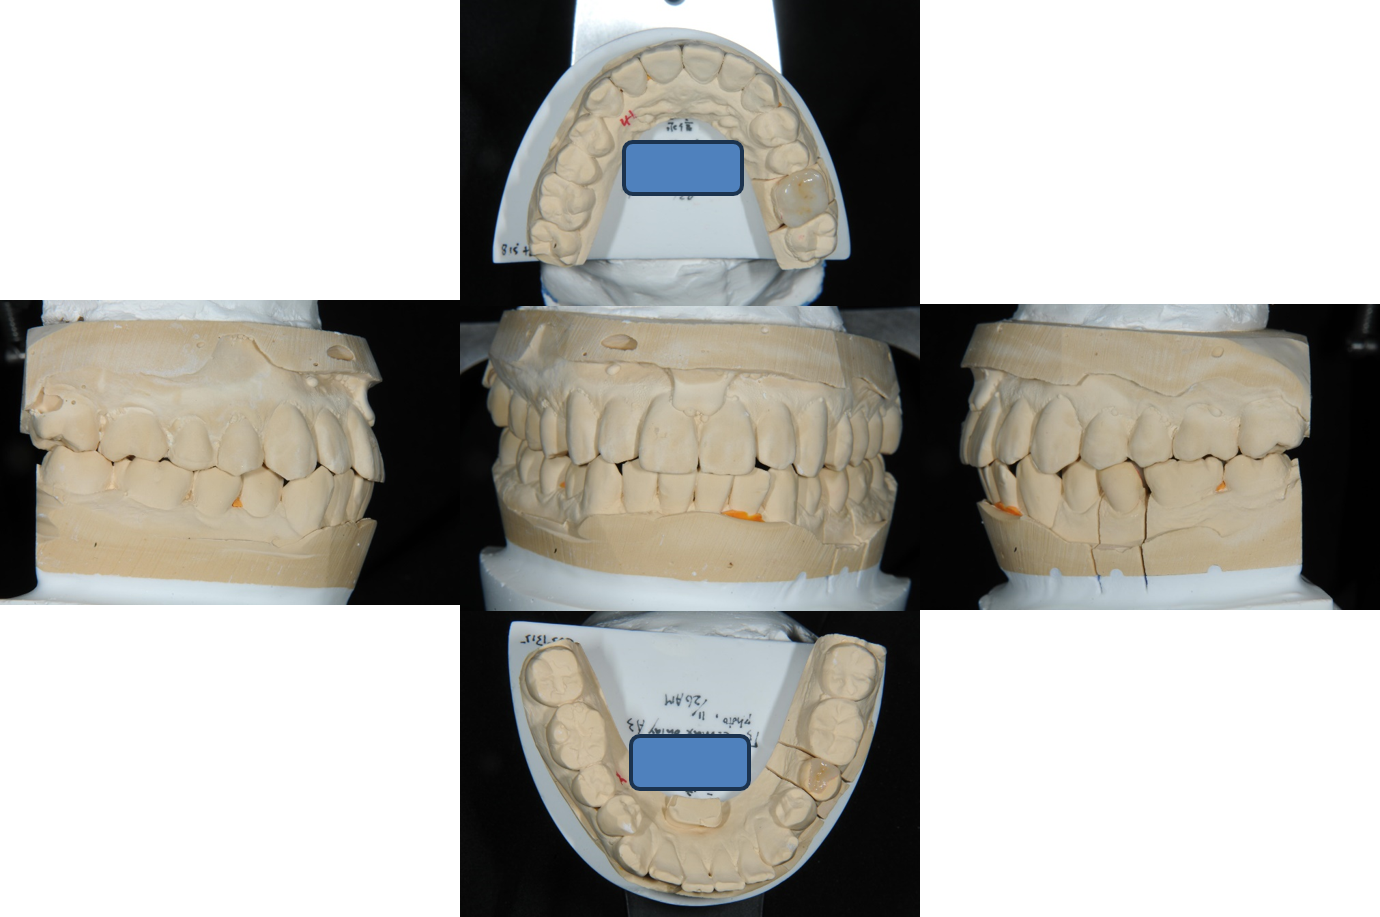

模型上咬合器

模型上製作陶瓷崁體